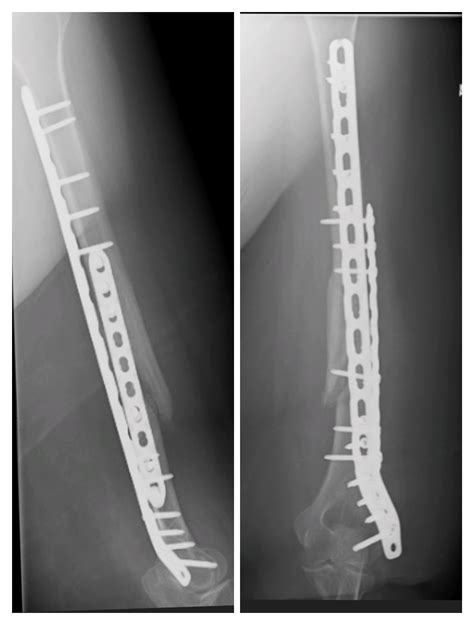

Seeing the bone through the plates : r/brokenbones